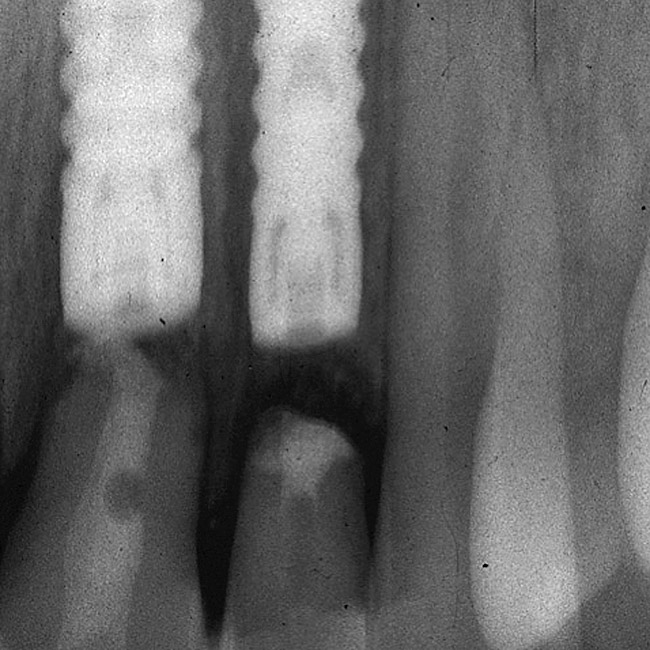

Figure 14  This patient exhibits ankylosed teeth Nos. 8, 9, and 10, but excellent bone.

Figure 14

Figure 15  Excellent bone levels.

Figure 15

Figure 16  Teeth Nos. 8, 9, and 10 were removed and immediate implants placed at the Nos. 8 and 10 sites.

Figure 16

Figure 17  Connective-tissue grafting in the pontic area of No. 9 and over the implant site No. 10.

Figure 17

Figure 18  Final restoration was achieved with a three-unit zirconia prosthesis: No. 8—implant abutment, No. 9—pontic, and No. 10—abutment.

Figure 18